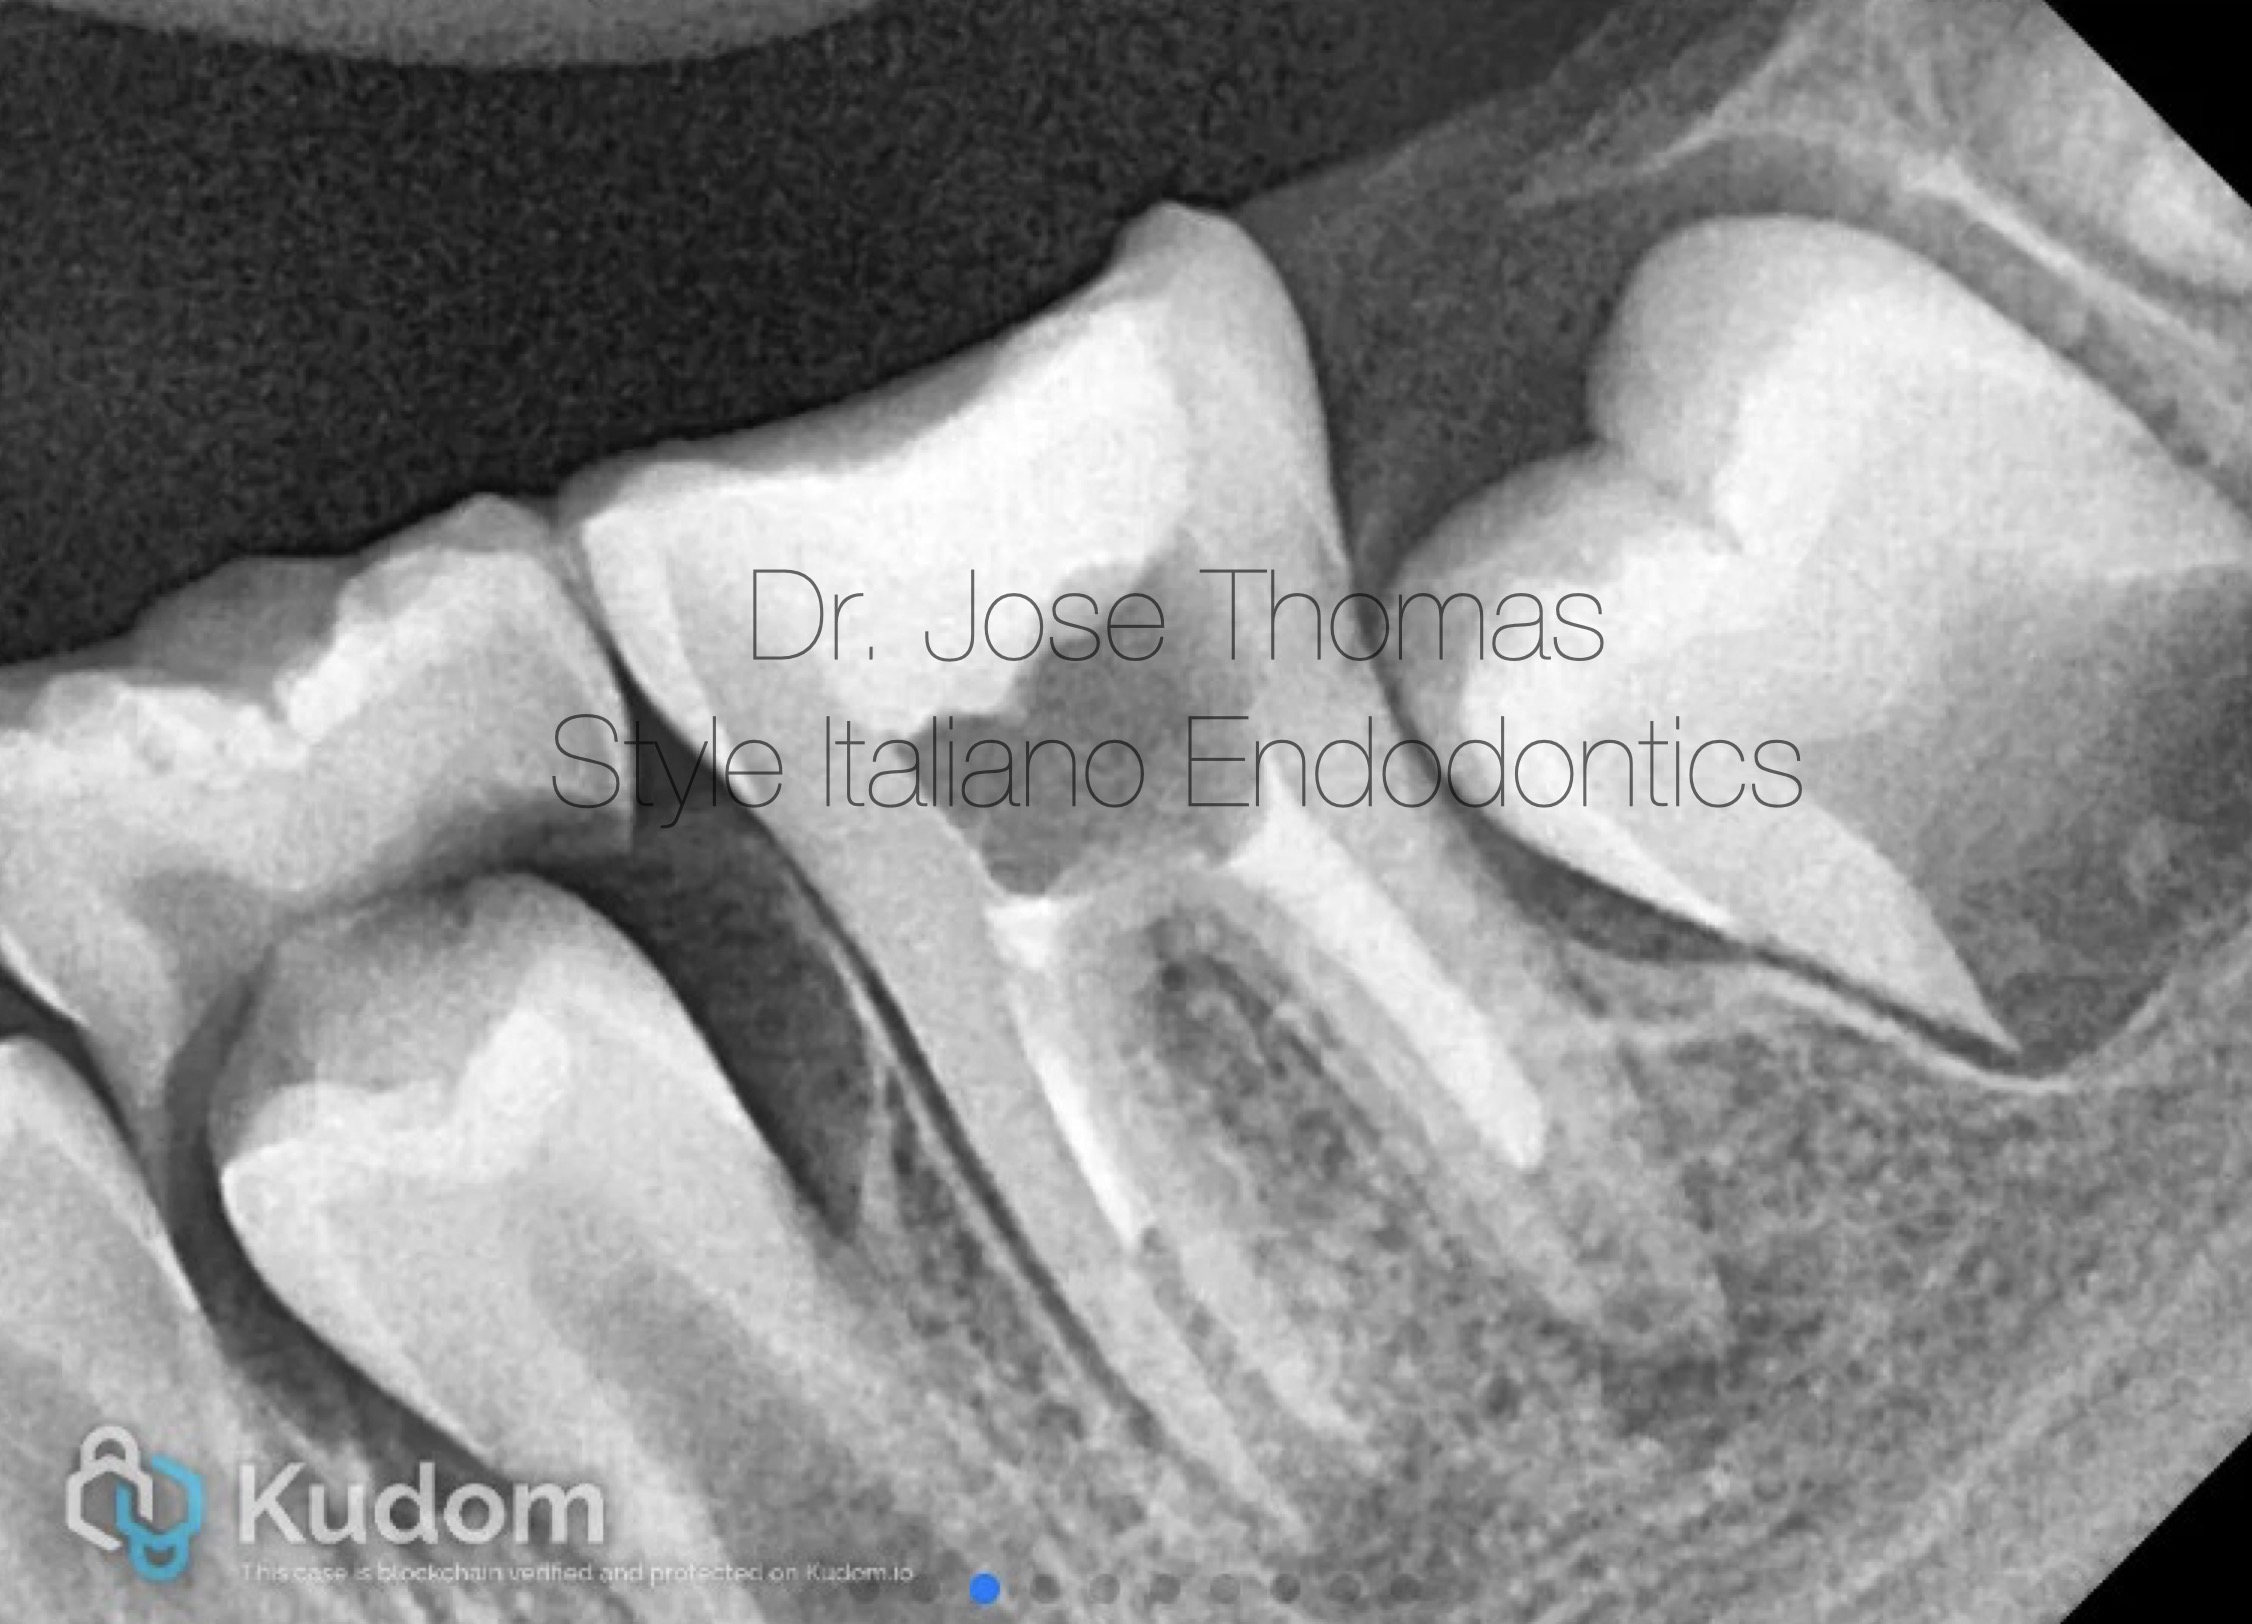

Follow-up radiograph at 30 months showed resolution of periapical lesion, and completion of root formation and establishment of lamina dura.

Xray IOPA at 30 months review shows resolution of periapical lesion, and completion of root formation and establishment of lamina dura